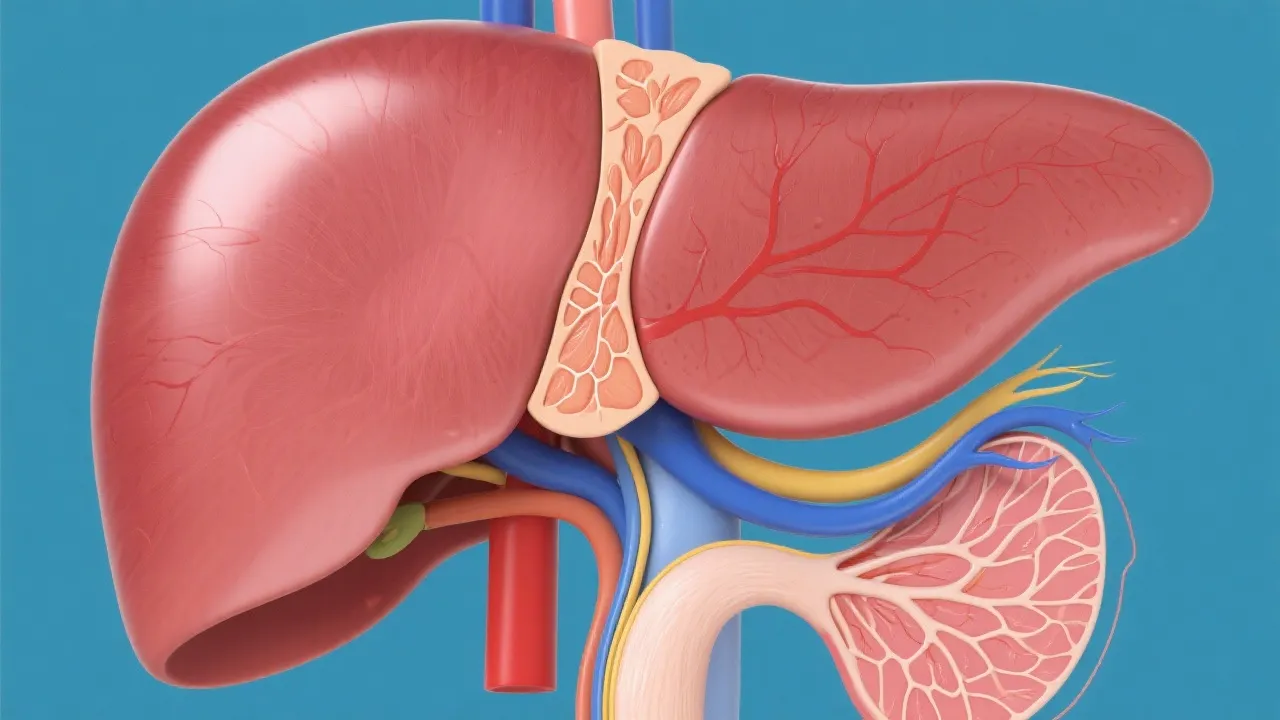

This article explores the intricate relationship between Non-Alcoholic Fatty Liver Disease (NAFLD) and Hepatocellular Carcinoma (HCC), two interconnected liver conditions that are increasingly prevalent. NAFLD is characterized by excess fat buildup in the liver, which can progress to HCC, a primary form of liver cancer. Understanding their connection is essential for early detection and management strategies.

A growing body of research indicates a strong connection between Non-Alcoholic Fatty Liver Disease (NAFLD) and Hepatocellular Carcinoma (HCC). NAFLD is recognized as the accumulation of excess fat in liver cells in individuals who consume little or no alcohol. Furthermore, prevalence rates have surged in recent years, making NAFLD one of the most common liver disorders in the world. It is estimated that about 25-30% of the global population is affected by NAFLD. Over time, NAFLD can progress to non-alcoholic steatohepatitis (NASH), fibrosis, cirrhosis, and potentially HCC, a primary form of liver cancer. The link between NAFLD and HCC is concerning due to the escalating rates of obesity and metabolic syndrome globally. Understanding this progression is vital for implementing effective prevention and treatment strategies to mitigate the risk of liver cancer.

NAFLD is caused by a variety of factors, including obesity, insulin resistance, metabolic syndrome, and genetic predispositions. The condition is diagnosed when more than 5% of hepatocytes showcase steatosis without significant alcohol use. The accumulation of fat in liver cells triggers a series of pathological processes, including oxidative stress, lipotoxicity, and inflammation. Initially, the process begins with simple steatosis, which can progress to NASH if left unmanaged. NASH, characterized by inflammation and liver cell damage, significantly increases the risk of progressing to cirrhosis and eventually HCC. The interplay between these processes is complex: inflammation further exacerbates insulin resistance, creating a vicious cycle that accelerates disease progression.

The progression from NAFLD to HCC is complex and multifaceted. Chronic inflammation and cell death in NASH create an environment conducive to cancer development. DNA damage, cellular turnover, and regenerative proliferation further contribute to this transformation. As cirrhosis sets in, the risk of developing HCC grows exponentially due to the sustained state of liver cell damage. Studies indicate that the development of HCC often occurs in the backdrop of cirrhotic liver disease, when the liver architecture is significantly altered. This creates an environment ripe for malignant transformation, characterized by the emergence of dysplastic nodules and subsequent fast-growing tumors.